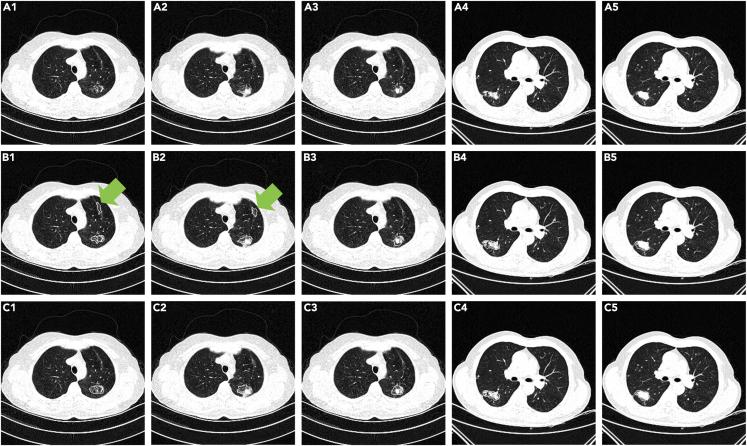

一种用于CT图像中肺炎、肺结节和肺结核自动分割的通用方法。

A general approach for automatic segmentation of pneumonia, pulmonary nodule, and tuberculosis in CT images.

Proposing a general segmentation approach for lung lesions, including pulmonary nodules, pneumonia, and tuberculosis, in CT images will improve efficiency in radiology. However, the performance of generative adversarial networks is hampered by the limited availability of annotated samples and the catastrophic forgetting of the discriminator, whereas the universality of traditional morphology-based methods is insufficient for segmenting diverse lung lesions. A cascaded dual-attention network with a context-aware pyramid feature extraction module was designed to address these challenges. A self-supervised rotation loss was designed to mitigate discriminator forgetting. The proposed model achieved Dice coefficients of 70.92, 73.55, and 68.52% on multi-center pneumonia, lung nodule, and tuberculosis test datasets, respectively. No significant decrease in accuracy was observed (p > 0.10) when a small training sample size was used. The cyclic training of the discriminator was reduced with self-supervised rotation loss (p < 0.01). The proposed approach is promising for segmenting multiple lung lesion types in CT images.

摘要

提出一种针对CT图像中肺部病变(包括肺结节、肺炎和肺结核)的通用分割方法将提高放射学的效率。然而,生成对抗网络的性能受到注释样本可用性有限以及判别器灾难性遗忘的阻碍,而传统的基于形态学的方法的通用性不足以分割各种肺部病变。设计了一种带有上下文感知金字塔特征提取模块的级联双注意力网络来应对这些挑战。设计了一种自监督旋转损失来减轻判别器遗忘。所提出的模型在多中心肺炎、肺结节和肺结核测试数据集上分别实现了70.92%、73.55%和68.52%的骰子系数。当使用小训练样本量时,未观察到准确性有显著下降(p>0.10)。通过自监督旋转损失减少了判别器的循环训练(p<0.01)。所提出的方法在分割CT图像中的多种肺部病变类型方面很有前景。